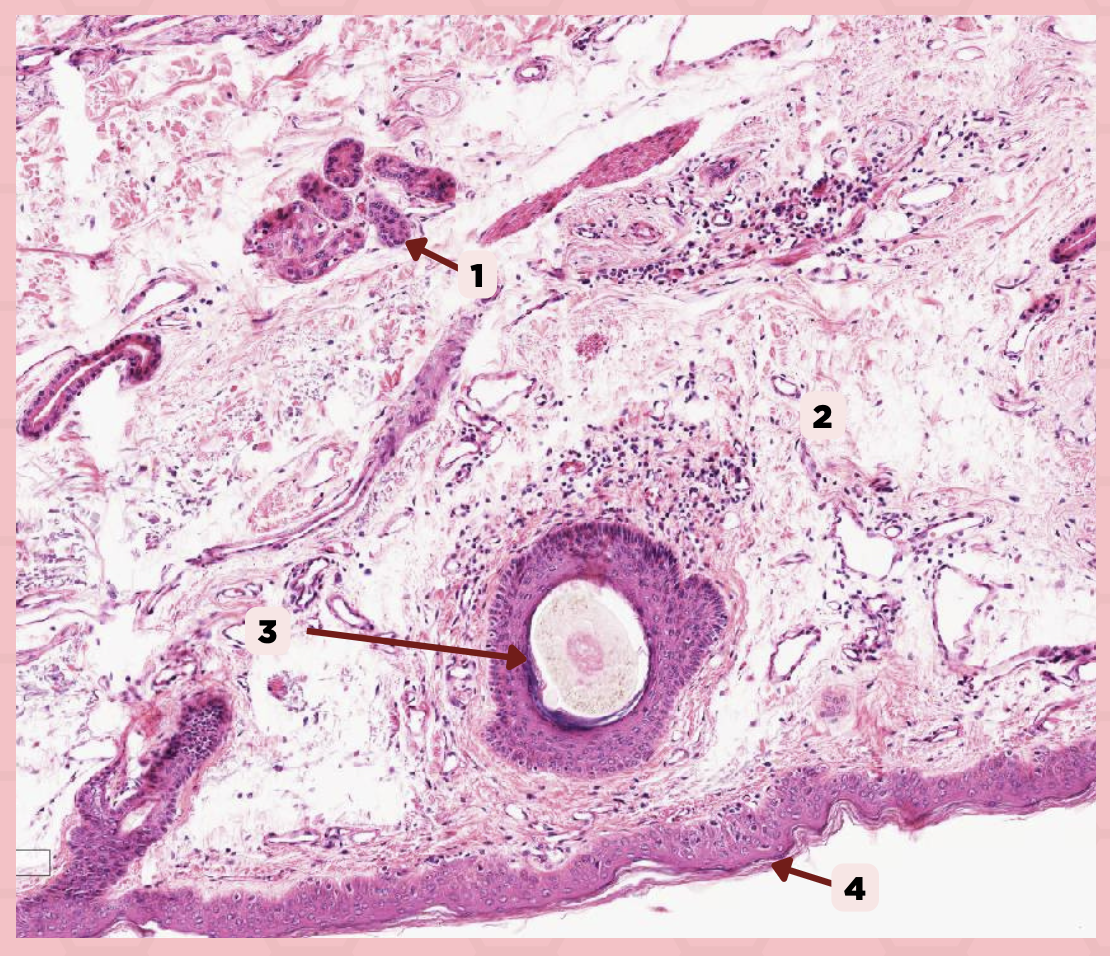

Lip

What specimen is being showed in the picture?

Epidermis

Identify the structure labeled as 1.

Dermis

Identify the structure labeled as 2.

Arrector Pilli Muscle

Identify the structure labeled as 3.

Hair Follicle

Identify the structure labeled as 4.

Sebaceous Glands

Identify the structure labeled as 5.

Lip

What is the specimen showed in the picture?

Epidermis

Identify the structure labeled as 1.

Dermis

Identify the structure labeled as 2.

Arrector Pilli Muscle

Identify the structure labeled as 3.

Hair Follicle

Identify the structure labeled as 4.

Sebaceous Glands

Identify the structure labeled as 5.